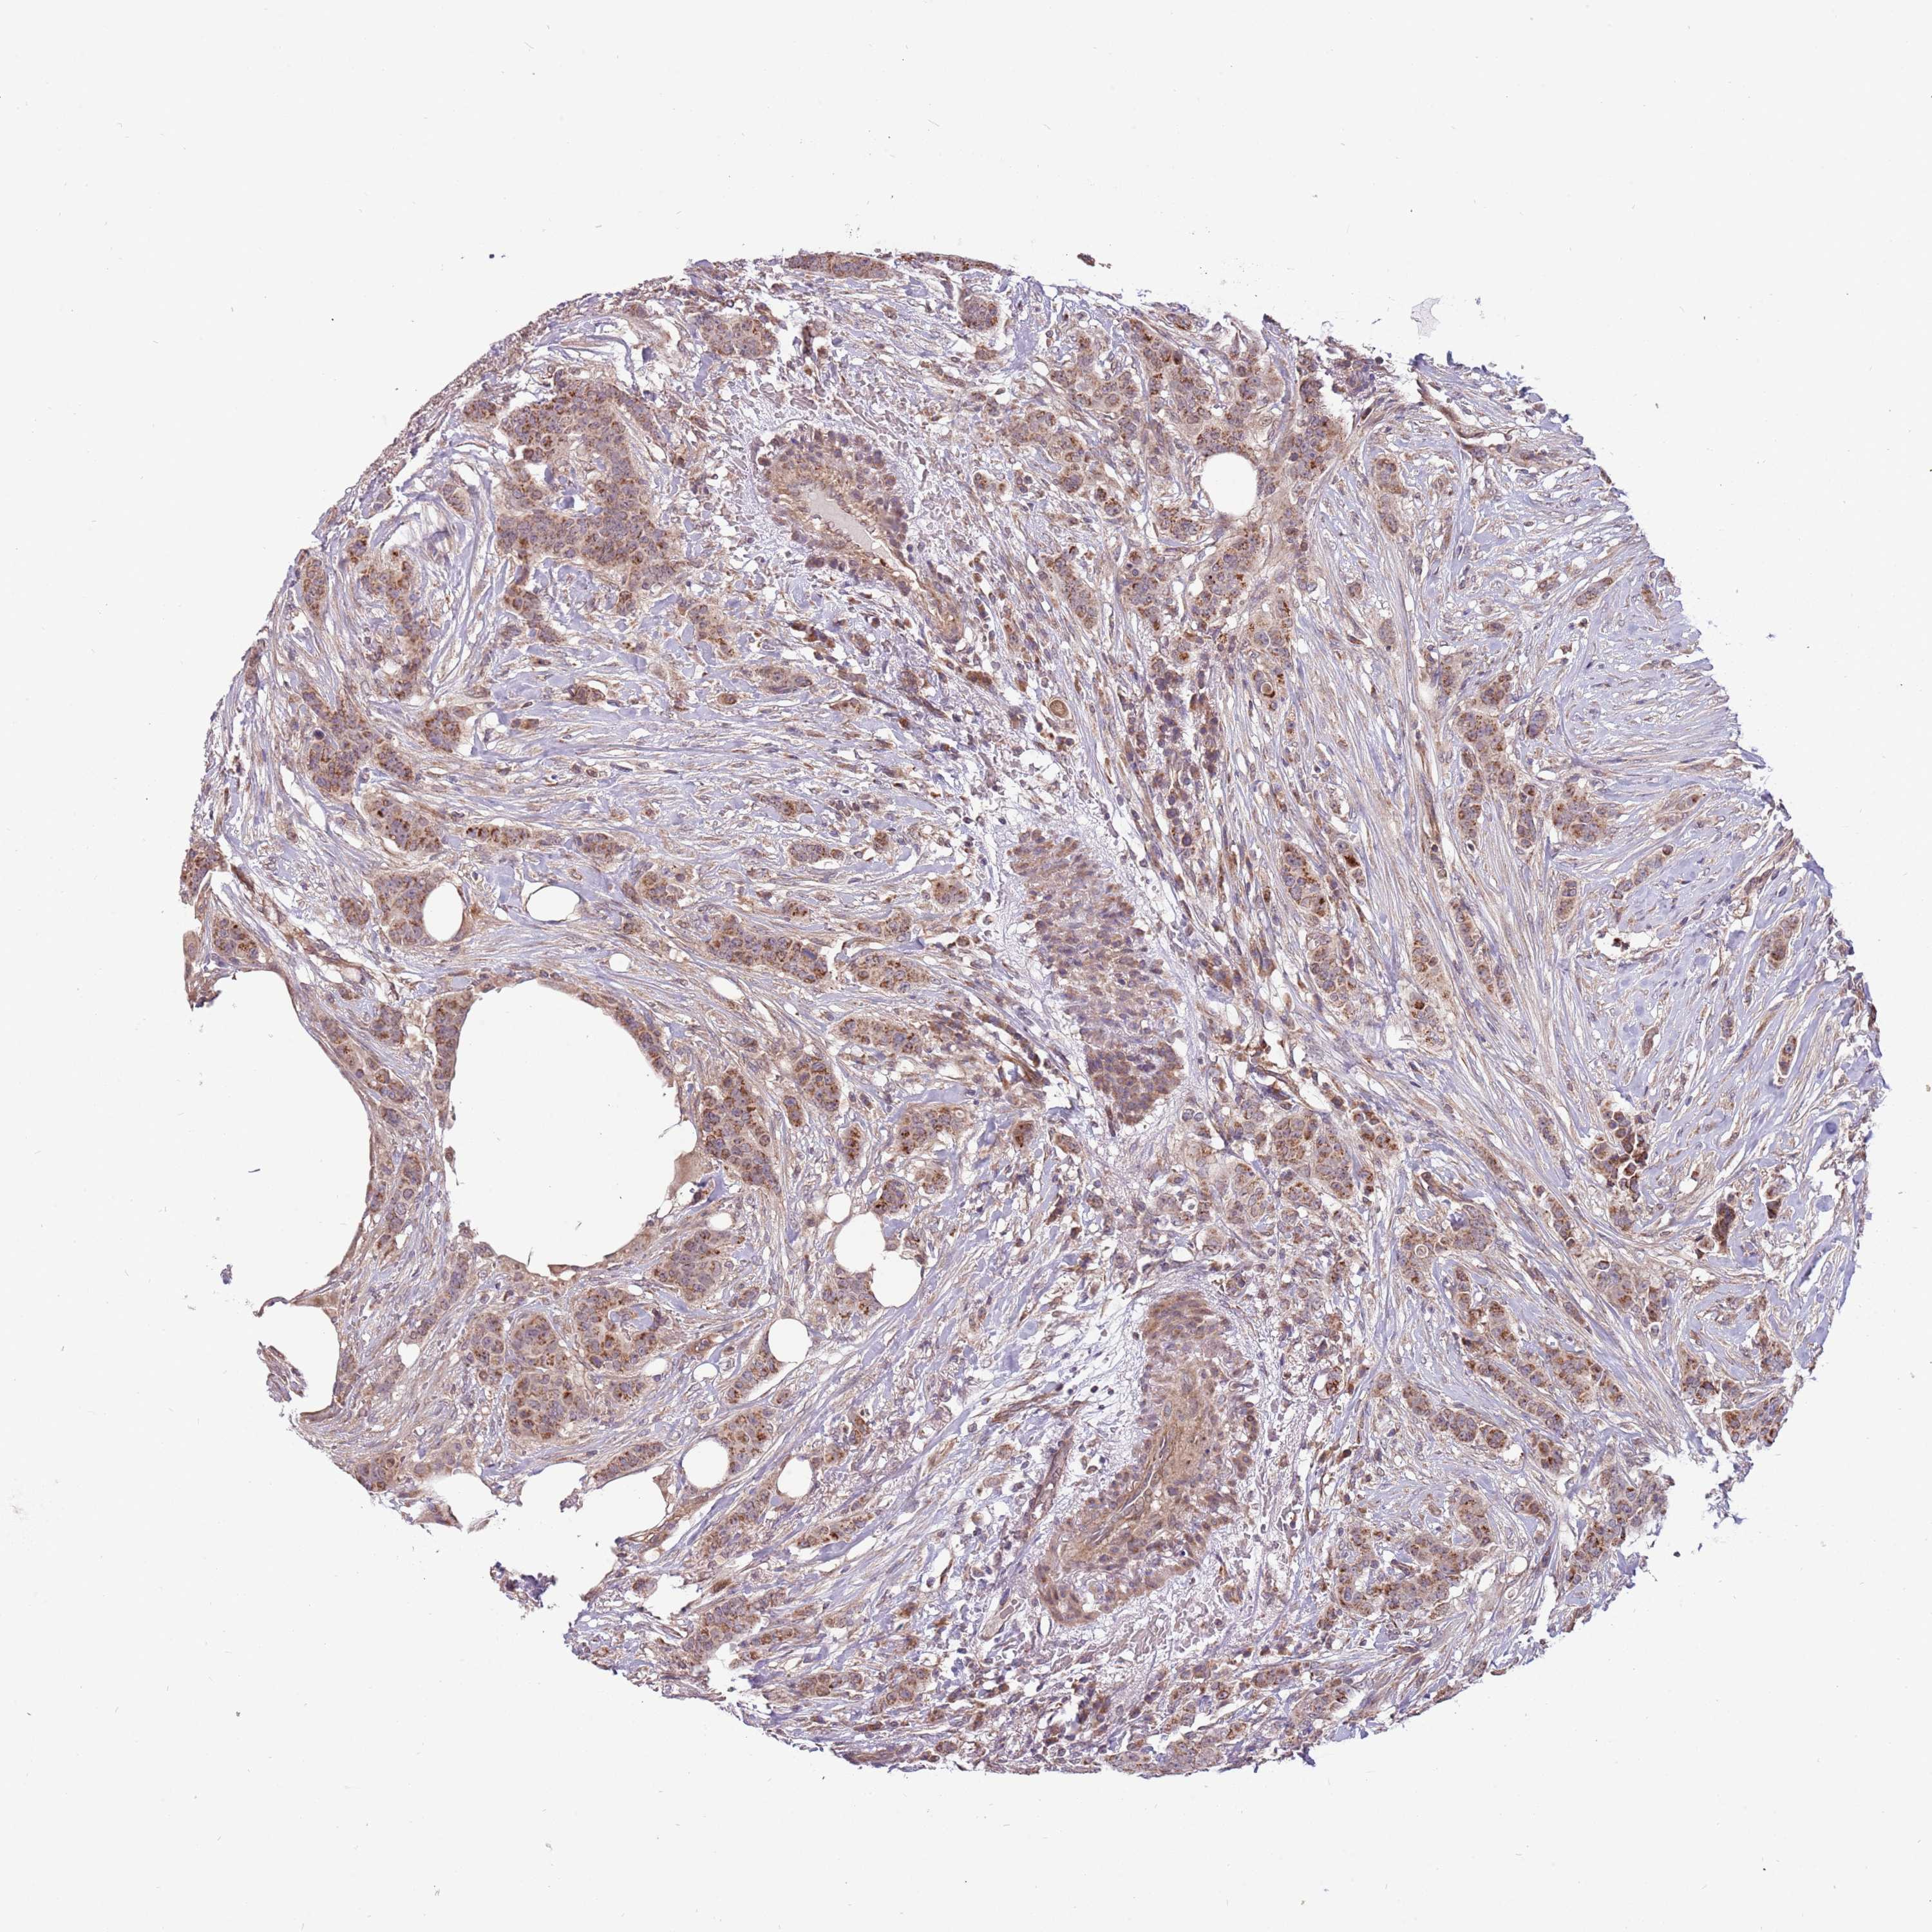

CANCER BREAST CANCER Show tissue menu

Breast cancer

Human cancer